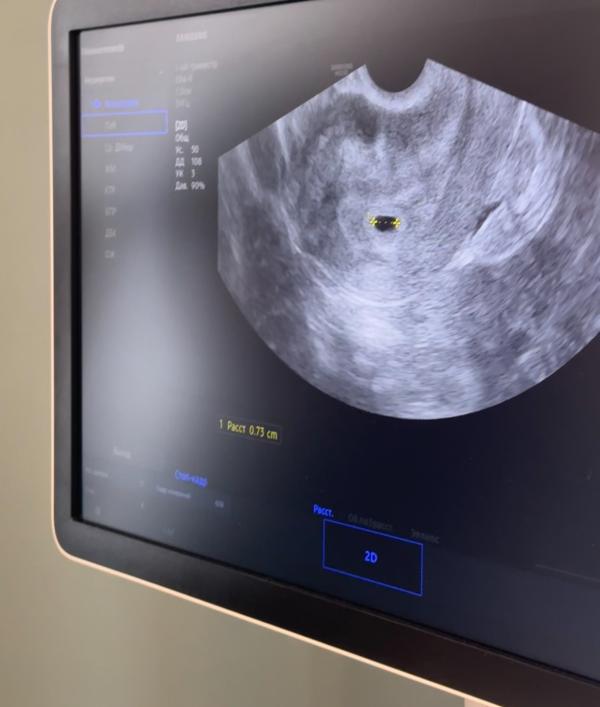

15 дпп

Сходила я значит на узи , показывает 1 плодное яйцо , второго пока нет ( сказали что через 10 дней может и 2 показаться , долго проверять не стала , есть риск что может второй на трубу ушел в таком случае типа ( внематочная ) но такое редко бывает сказала - но как врач она должна была сказать !

Так же у меня прогестерон 16 ( прям бесит - но поддержку оставляем. Сказала отдыхать , лежать , думать позитивно ..